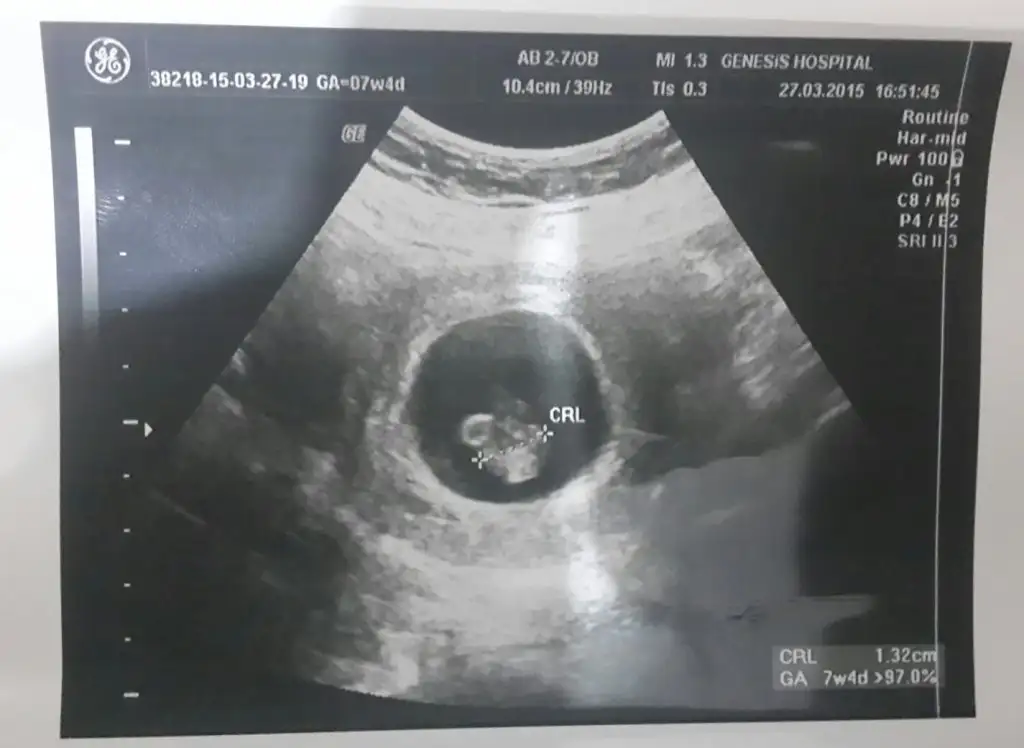

'Arkadaşlar bugün ultrasonda 6 bucuk haftalık oldugunu söyledi doktorum.Tahminde bulunabilirmisiniz..

6 haftalık ultrason görüntüsü tahminde bulunabilir misiniz